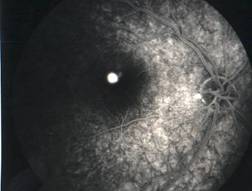

RETINITIS PIGMENTOSA |

Retinitis pigmentosa is the most common of a group of hereditary progressive retinal degenerations or dystrophies. There is considerable variation and overlap among the various forms of retinitis pigmentosa. Common to all of them is progressive degeneration of the retina, specifically of the light receptors, known as the rods and cones. The rods of the retina are involved earlier in the course of the disease, and cone deterioration occurs later. In this progressive degeneration of the retina, the peripheral vision slowly constricts and central vision is usually retained until late in the disease. Etiology

Ophthalmic features